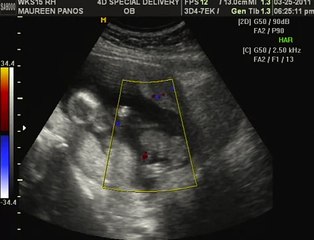

16 weeks Ultrasound - It's a Boy!!!